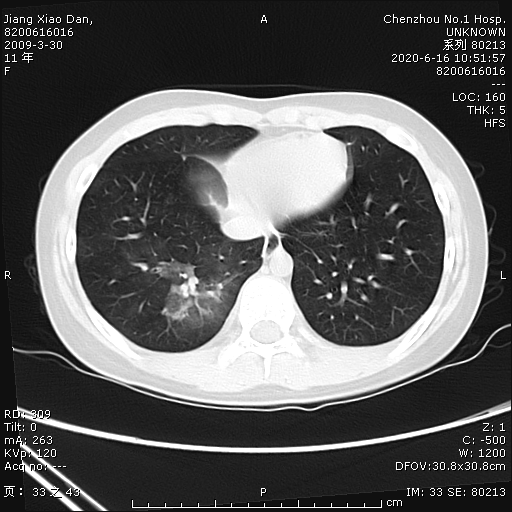

小單因?yàn)椤翱人?、吐?天,嘔吐1天”于6月11日到郴州市第一人民醫(yī)院就診,經(jīng)胃鏡檢查提示糜爛出血性胃炎,考慮“上消化道出血”,收入兒童醫(yī)院消化內(nèi)科住院治療。經(jīng)給予“阿莫西林、克拉霉素、奧美拉唑”聯(lián)合根治幽門螺桿菌治療,患兒仍咳出兩次鮮紅色血液混合粘液,考慮患兒并非單純上消化道出血,遂請(qǐng)兒童呼吸二區(qū)會(huì)診,擬“咯血查因”,轉(zhuǎn)入兒童呼吸二區(qū)繼續(xù)治療,入科后急行胸部血管成像cta檢查示右肺下葉肺出血改變,并未發(fā)現(xiàn)異常血管。右肺下葉支氣管后基底段鑄形軟組織密度影充填:支氣管腔內(nèi)積血?